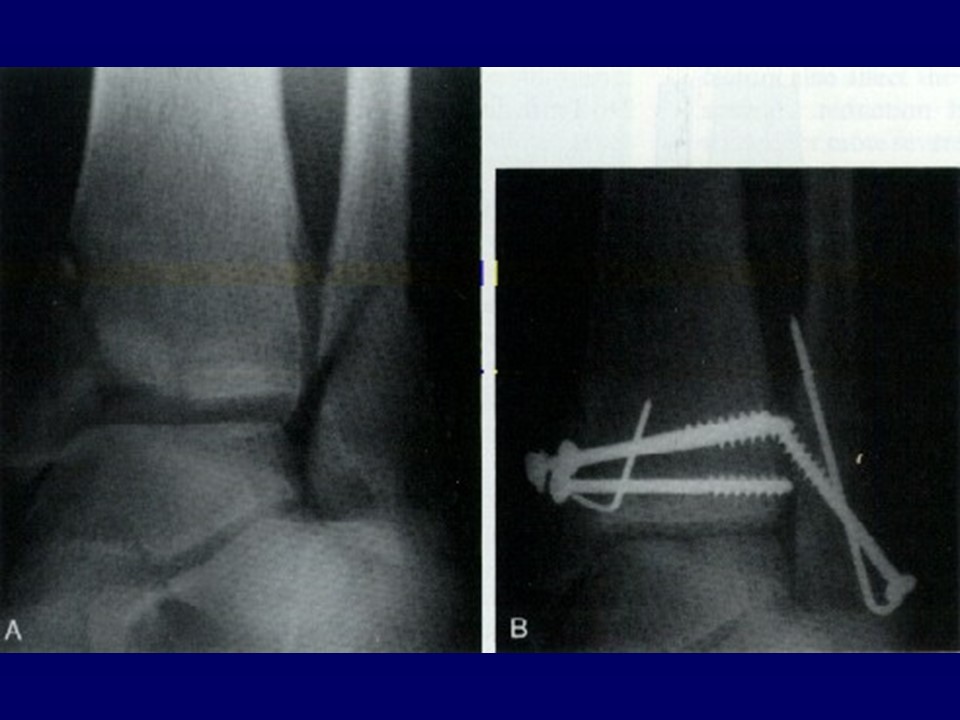

踝关节骨折的治疗PPT

Ramsey and Hamilton: 1 毫米的外移, 胫距关节接触面积将减少42%